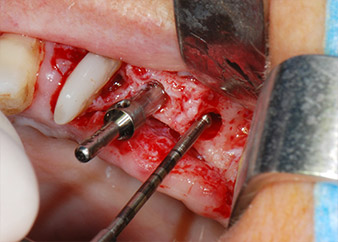

Prior to implant placement, infected tissue was removed from the alveolar bone in the implant site and around the abutment teeth with an insert originally designed for bone shaping and collecting bone chips (Piezomed, insert B5) (Figs. 6 and 7).

IImplant beds were prepared at sites 25 and 26 with rotary instruments, used in a contra-angle handpiece with a 20 : 1 transmission ratio with an updated powerful implant motor (Implantmed, W&H) (Fig. 8).

The final preparation next to the sinus was again carried out with a piezoelectric instrument (Piezomed, insert S2).

Prior to implant placement, and following verification of an intact Schneiderian membrane (Fig. 9), the internal sinus floor was augmented at both implant sites by means of xenogeneic bone substitute material (Bio-Oss, Geistlich Biomaterials) (Fig. 10).